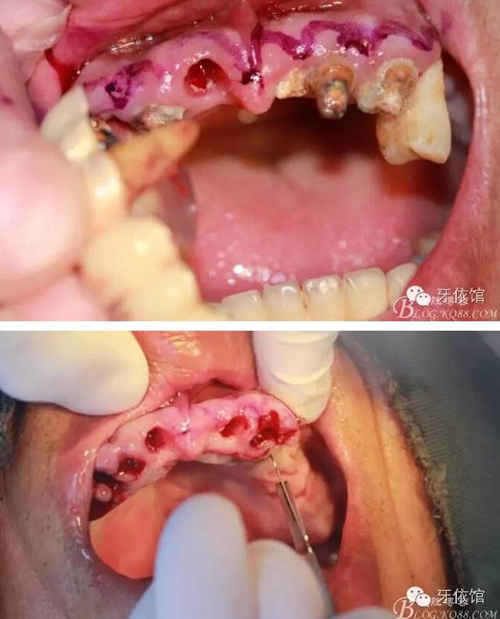

術(shù)中口內(nèi)照

降低骨高度,左右1,2骨寬度嚴(yán)重不足,決定將前牙2——2區(qū)間植體植在切牙孔內(nèi)

這個(gè)角度看1,2牙位骨寬度是不是很???僅2mm

用擴(kuò)孔鉆去除切牙孔內(nèi)神經(jīng)纖維和血管